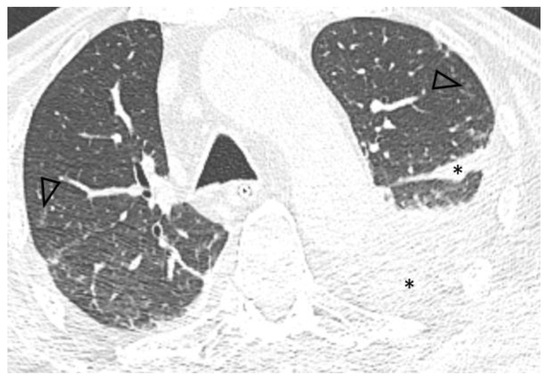

Introduction: Intravesical Bacillus Calmette-Guérin (BCG) instillation is the most effective adjuvant therapy for superficial urinary bladder carcinoma, prolonging disease-free survival. Although it is usually well tolerated, moderate to severe local or systemic infectious complications, including sepsis involving multiple organs, may occur. Case report: [...] Read more.

Introduction: Intravesical Bacillus Calmette-Guérin (BCG) instillation is the most effective adjuvant therapy for superficial urinary bladder carcinoma, prolonging disease-free survival. Although it is usually well tolerated, moderate to severe local or systemic infectious complications, including sepsis involving multiple organs, may occur. Case report: We report the unusual case of a man in his mid ‘70s who presented with septic shock and severe acute respiratory failure requiring intubation. Lack of response to antibiotics, history of intravesical BCG instillation and consistent imaging findings led to further investigations, with bronchoalveolar lavage (BAL) fluid polymerase chain reaction (PCR) results indicating pneumonitis due to Mycobacterium bovis dissemination. Prompt anti-tuberculosis treatment combined with corticosteroids resulted in significant clinical and radiological improvement, supporting the diagnosis of disseminated BCG infection. Conclusions: Due to its non-specific clinical presentation and the relatively low diagnostic yield of conventional microbiological tests, a high index of suspicion is required for prompt diagnosis and treatment of systemic BCG infection. PCR-based assays for mycobacterial DNA identification may represent a valuable tool facilitating timely diagnosis of this uncommon, yet potentially life-threatening infection. Full article

Show Figures

Figure 1